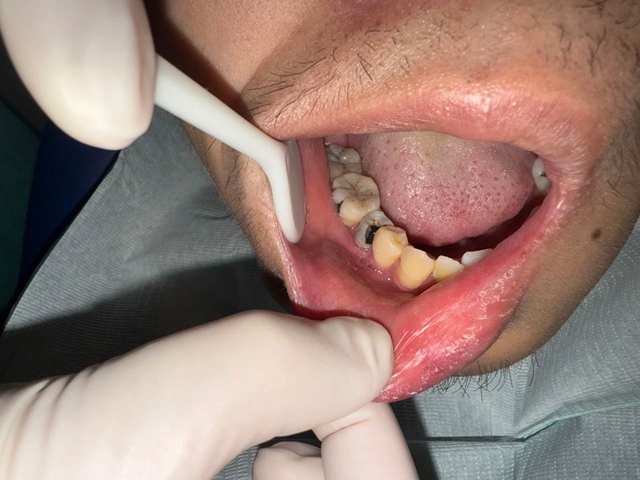

接诊的罗艳燕副教授检查发现,包块已形成3.5×4cm的脓肿,按压时脓液竟从口腔内侧和面部皮肤两处同时溢出,形成了可怕的“贯通性瘘管”。

罗艳燕通过细致检查,很快锁定了罪魁祸首。口内检查显示,45牙存在深龋,已经烂到牙髓腔,叩击时剧烈疼痛,牙齿松动明显,冷热刺激毫无反应——这是典型的牙髓坏死表现。更关键的是,颊侧牙龈的瘘管探针能直接通到牙根尖部。

影像学检查进一步揭开真相:根尖X线片发现45牙根尖有5mm×7mm的暗影;CBCT清晰显示颊侧骨板已被破坏,感染顺着咬肌前间隙扩散,形成了的脓腔,最终突破皮肤形成面部瘘口。血常规检查中白细胞、中性粒细胞和CRP等感染指标均显著升高,证实了严重的细菌感染状态。

术前影像学资料